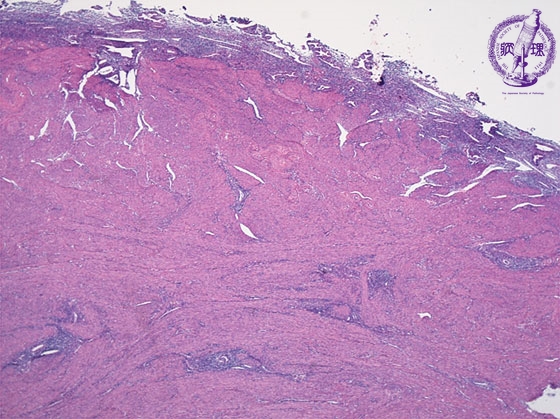

- ★(2)Adenomyosis

Histology (HE stain, low power) Ectopic endometrial glands and stromal cells in the myometrium (yellow dotted line).